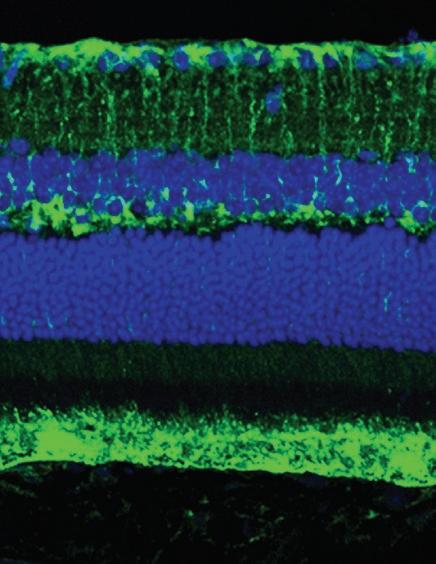

Mouse retina glial cells (top), a non-neuronal cell type abundant in the nervous system, and retinal pigment epithelium cells (bottom) stained to show the presence of PHGDH (green).